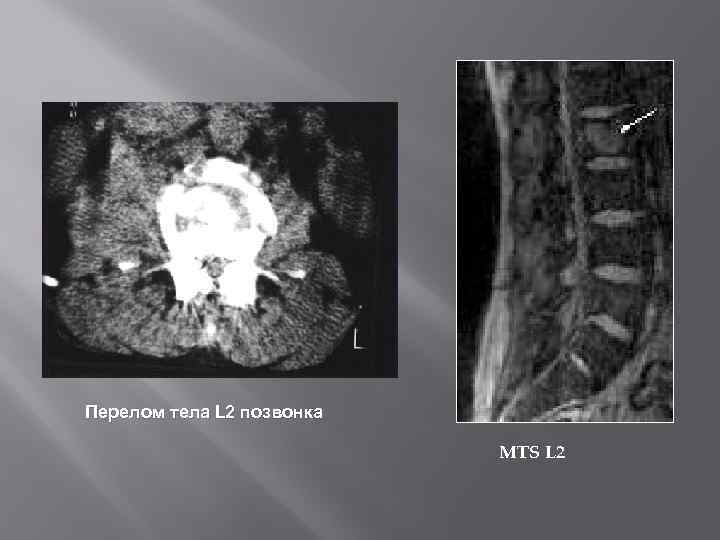

Перелом тела L 2 позвонка MTS L 2